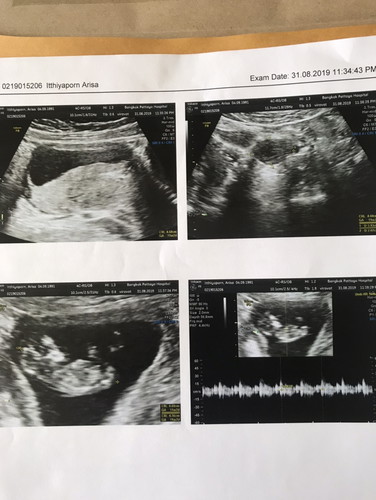

สอบถามหน่อยคะ ว่า12วีคกับอีก3วัน สามารถซาวด์รู้เพศไหมคะ ท้องแรกตื่นเต้น หมอนัดวันอาทิตย์นี้ ส่วนภาพแค่อ้างอิงคะซาวด์ตอน11วีคกับ2วัน หมอบอกว่าลูกแข็งแรงมากเเขนขาครบแล้ว

บางคนเห็นแล้วนะคะ รอดูว่าน้องจะอ้าให้เห็นไหม

จะซาวเห็นเพศชัดเจนตอนช่วง18-20วีคขึ้นไปค่ะ